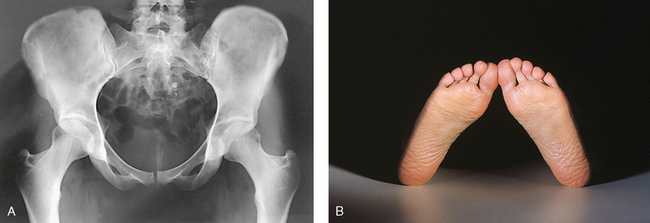

• Unless contraindicated because of trauma or pathologic factors, medially rotate the feet and lower limbs about 15 to 20 degrees to place the femoral necks parallel with the plane of the image receptor (IR) (Figs. 7-15 and 7-16). Medial rotation is easier for the patient to maintain if the knees are supported. The heels should be placed about 8 to 10 inches (20 to 24 cm) apart.

Fig. 7-15 A, AP pelvis with femoral necks and trochanters poorly positioned because of lateral rotation of limbs. B, Feet and lower limbs in natural, laterally rotated tabletop position, causing poor profile of proximal femora in A.

Fig. 7-16 A, AP pelvis with femoral necks and trochanters in correct position. B, Feet and lower limbs medially rotated 15 to 20 degrees, correctly placed with upper femora in correct profile in A.